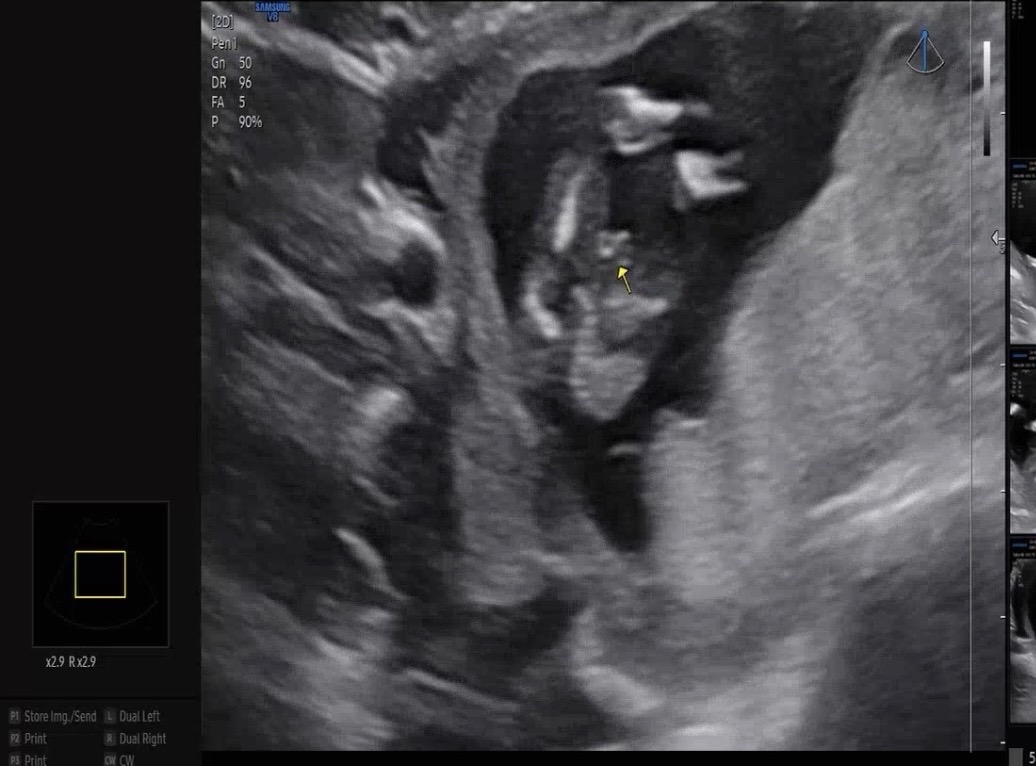

초음파 한번 봐주세용 ㅎㅎ

13주0일에 찍은 초음파예요 ㅎㅎ 의사샘은 옆에 알이 안보여서 애매하다고 이시기엔 딸도 대음순이 튀어나와있을수도 있다고 하셨는데 여러분들이 보시기엔 어떠신가여 ,,